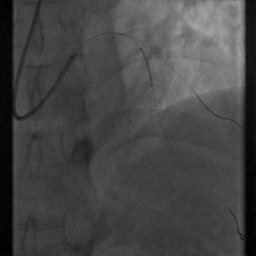

7.择2.5*15mm球囊送至D1开口处,以6atm*8s扩张

8.将支架囊送至支架近段,对吻扩张

重复造影:前向血流TIMI Ⅲ级,支架贴壁良好,无夹层、残余狭窄等。